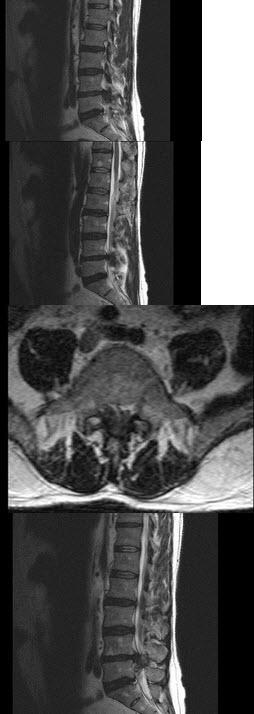

78、单项选择题

男,65岁,背痛半月余,结合影像学检查,最可能的诊断是()

A.脊椎结核

B.脊柱转移瘤

C.化脓性脊柱炎

D.骨质疏松性椎体骨折

E.脊椎退行性变

点击查看答案